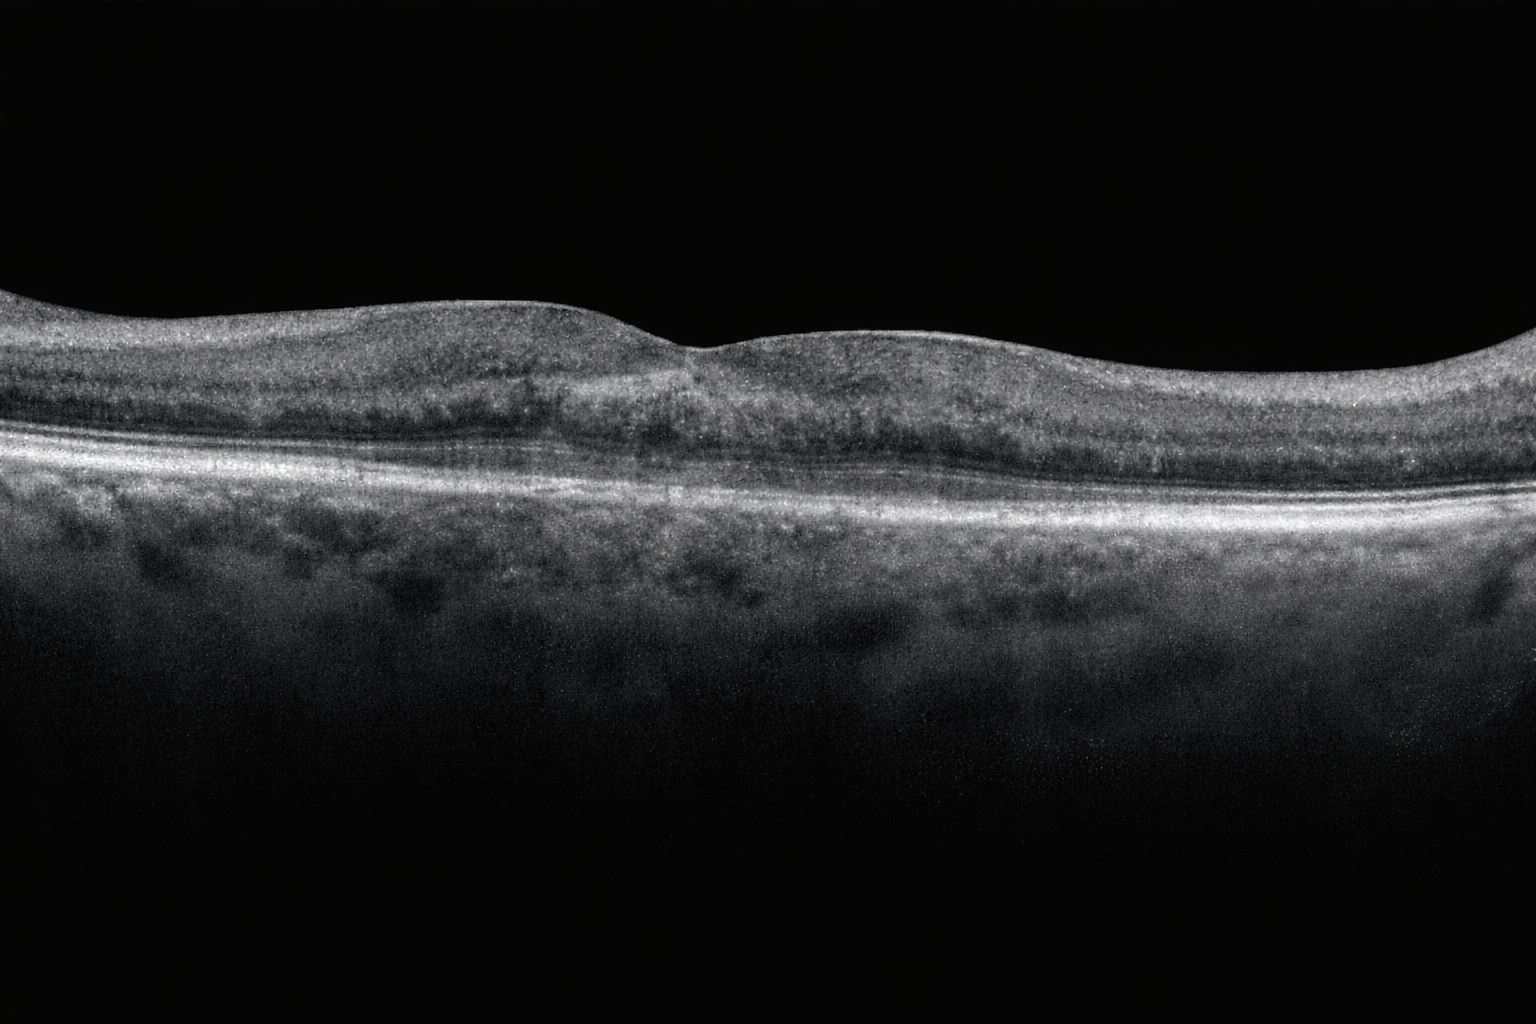

Her iki gözde doğuştan bu yana görme problemleri olan 11 yaşındaki erkek hastanı ...